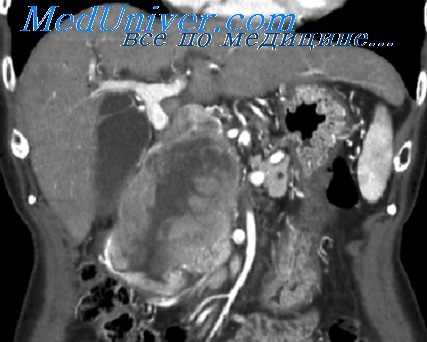

В 2016 году группой ученых из Германии, Швеции и Финляндии было проведено исследование, по результатам которого были названы наиболее распространенные места локализации метастазов рака желудка:

- Печень — 48%.

- Брюшина — 32%.

- Легкие — 15%.

- Кости — 12%.

Локализация метастазов зависит от типа опухоли. Так, при раке кардии (места перехода пищевода в желудок) у мужчин опухолевые клетки чаще распространяются в легкие, нервную систему и кости. Опухоли в других частях органа склонны метастазировать в брюшину. Перстневидноклеточный рак чаще метастазирует в брюшину, кости и яичники, реже — в легкие и печень. В печени и брюшине обычно обнаруживают одиночные метастазы, в то время как метастазы в легких часто сочетаются с метастазами в печени.

- Компьютерная томография хорошо обнаруживает метастазы в костях, но может также показать очаги и в мягких тканях.